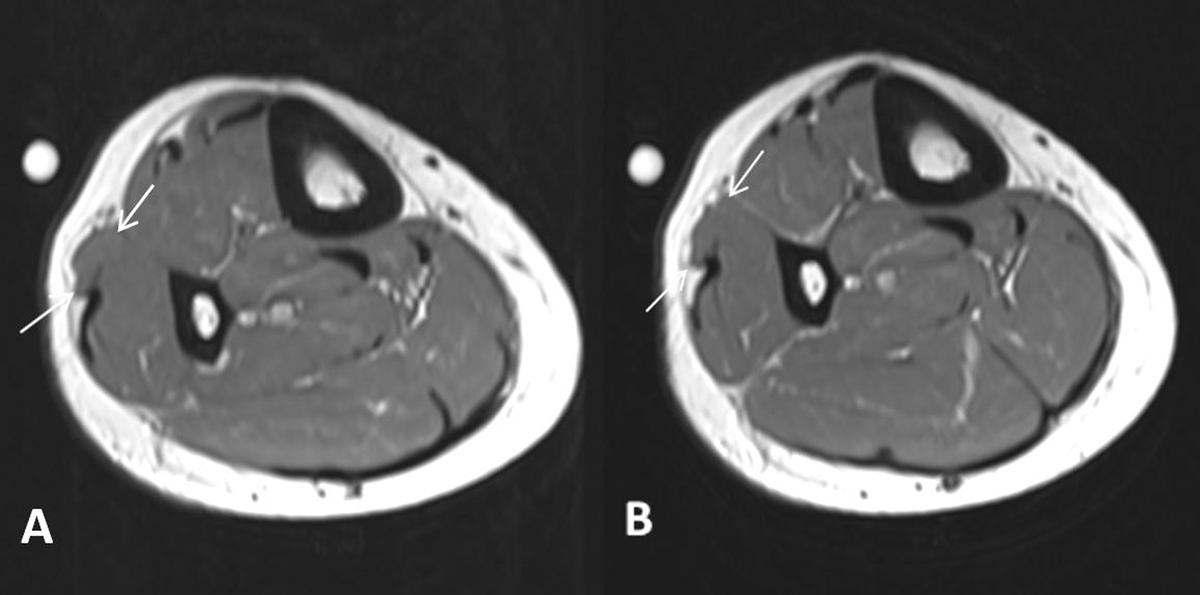

A 42-year-old woman was referred for magnetic resonance imaging (MRI) for evaluation of a painless soft-tissue swelling on the lateral side of the lower leg. The lesion had been present for many years and was more prominent in standing position. There was no history of trauma. A skin marker was placed at the soft-tissue lump in standing position. MRI showed subtle bulging of the contour of the peroneus longus muscle belly (Figure 1A, white arrow). The lesion was iso-intense to muscle tissue on all pulse sequences. There was no volume increase upon peroneus longus muscle contraction in supine position (Figure 1B). Subsequent dynamic ultrasound in standing position confirmed protrusion of peroneus longus muscle tissue (white arrow) through a fascial defect (Figure 2A). The lesion was barely visible in supine position and could be completely reduced upon compression with the ultrasound probe (Figure 2B). The muscle protrusion appeared more pronounced in standing position (supplementary video). Clinical examination and imaging were characteristic of peroneus longus muscle herniation.

Figure 1